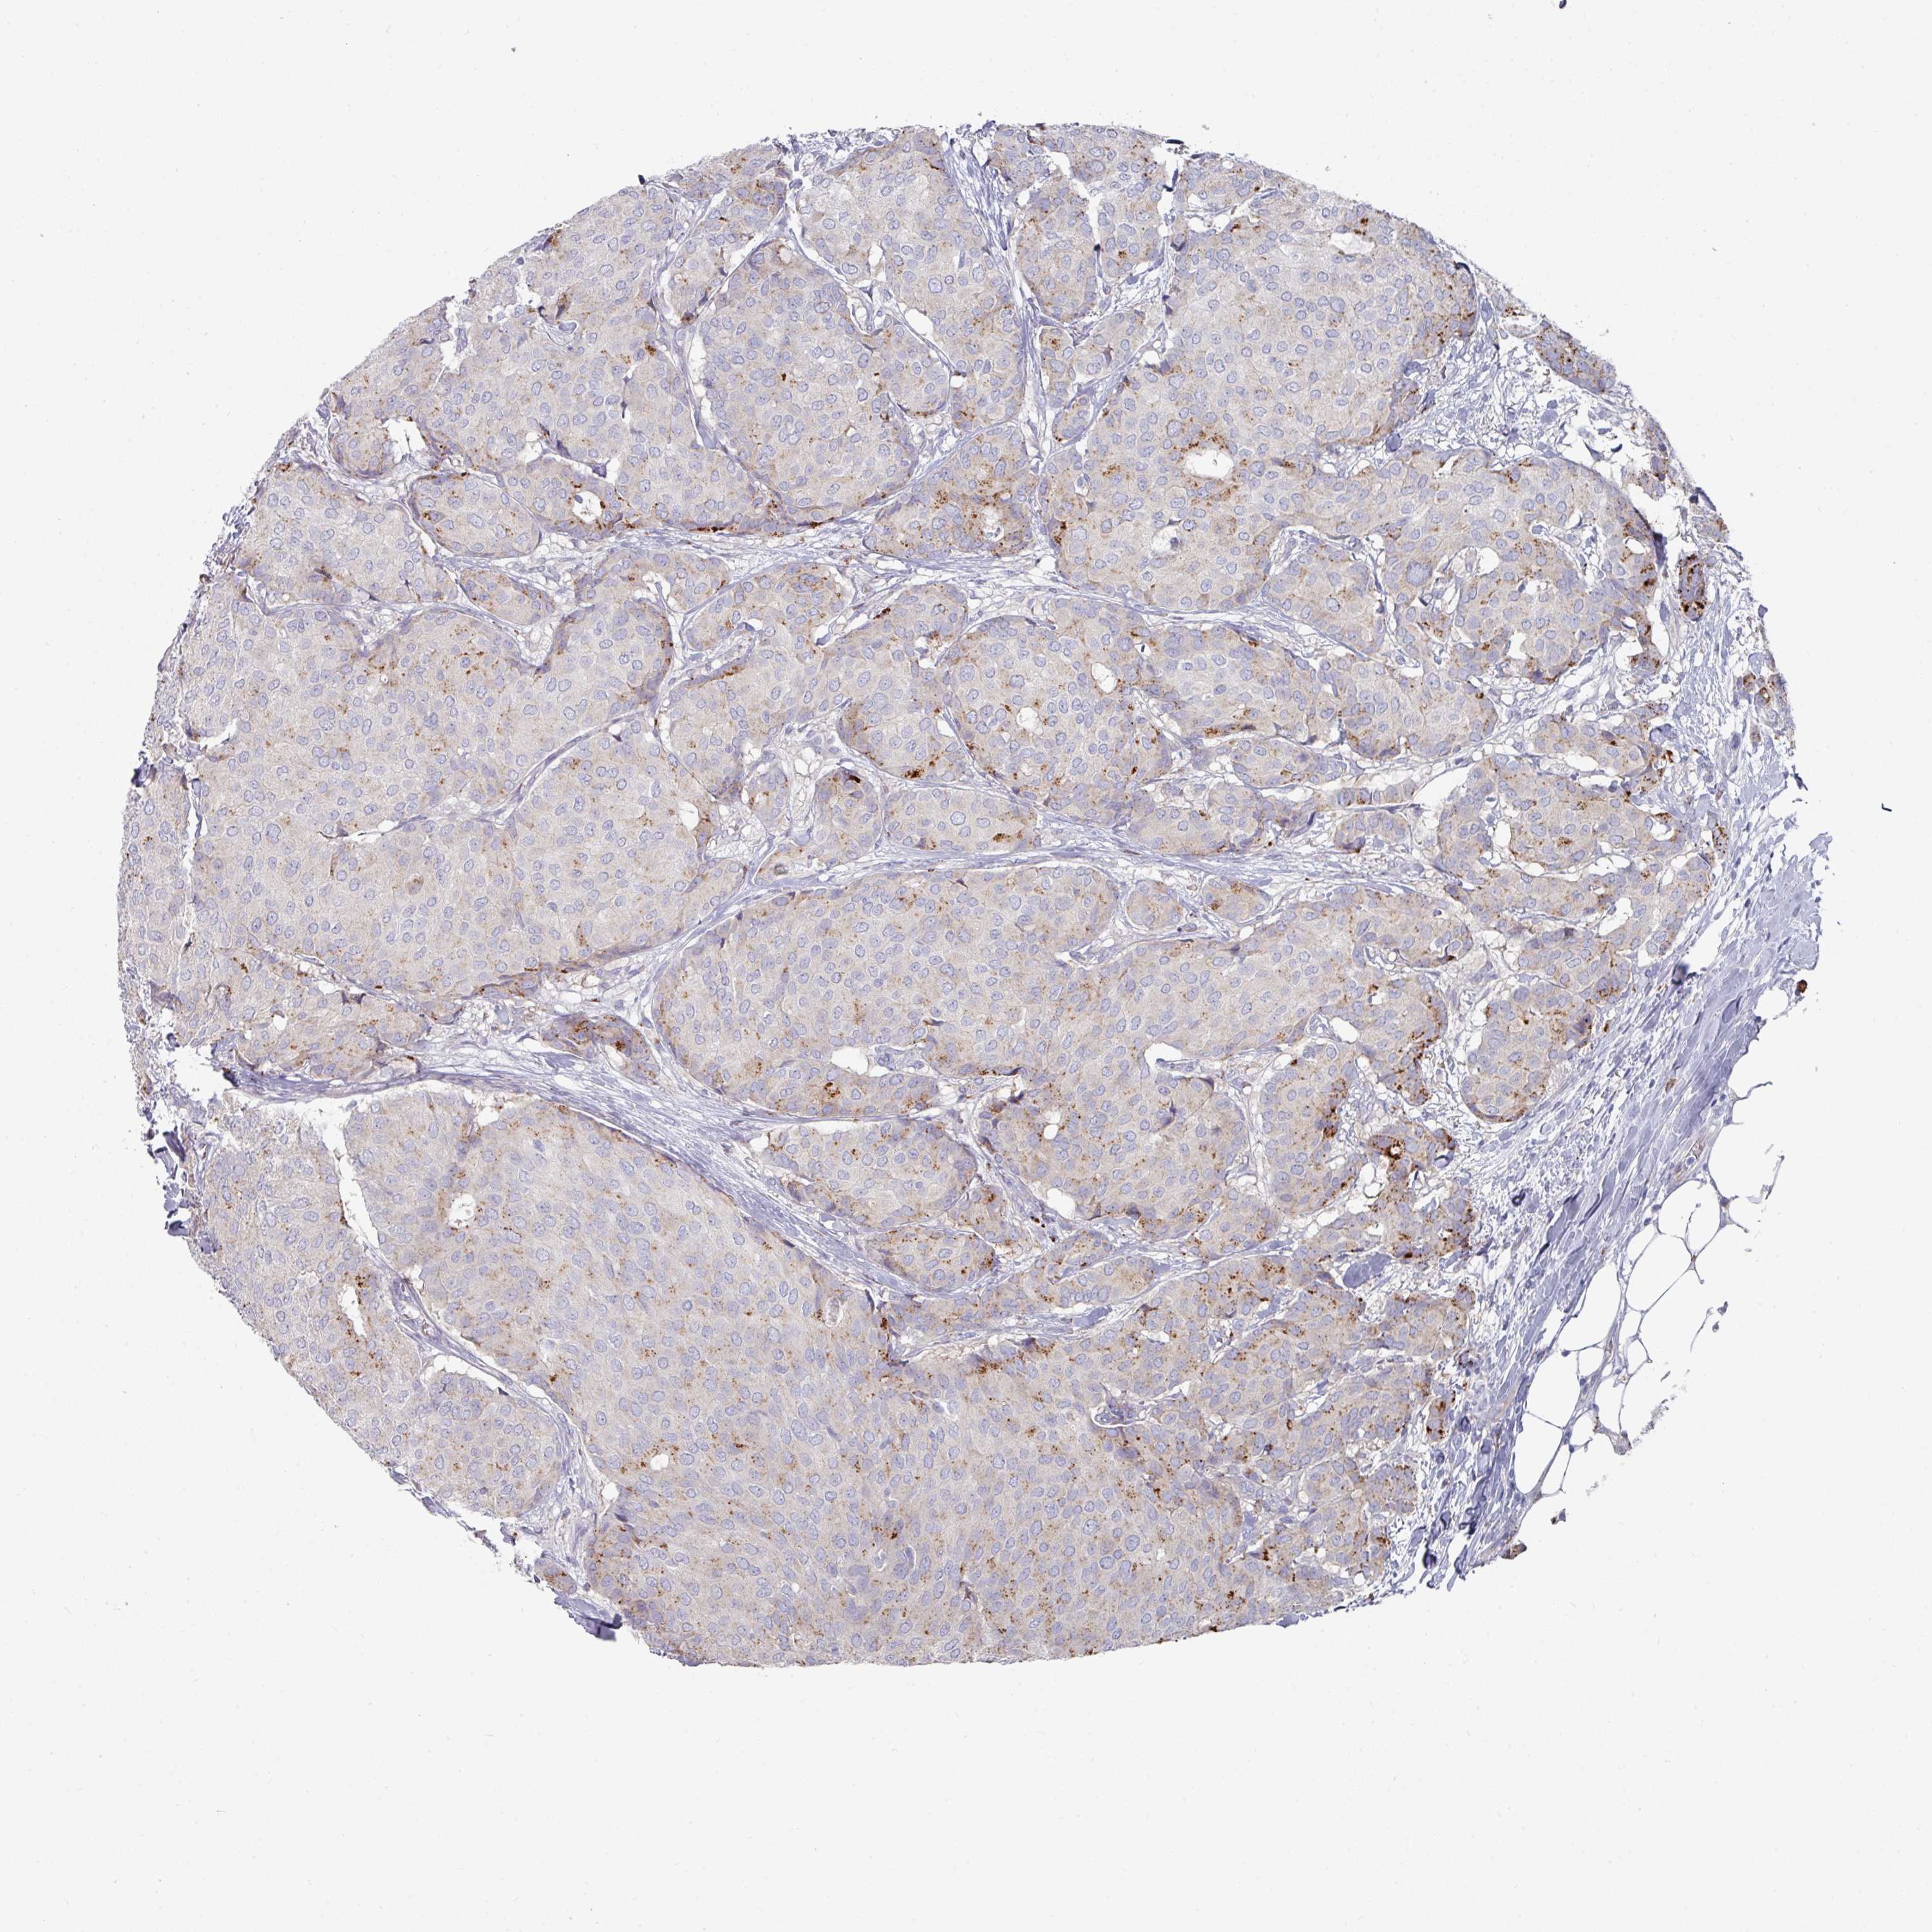

CANCER BREAST CANCER Show tissue menu

BRCA TCGA BRCA VALIDATION PROTEIN EXPRESSION

Breast cancer

Human cancer